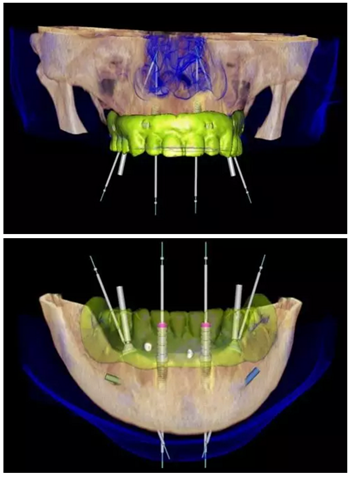

數(shù)字化治療方案設(shè)計(jì)

使用NobelClinician針對(duì)上頜及下頜分別進(jìn)行數(shù)字化的種植修復(fù)方案設(shè)計(jì)。